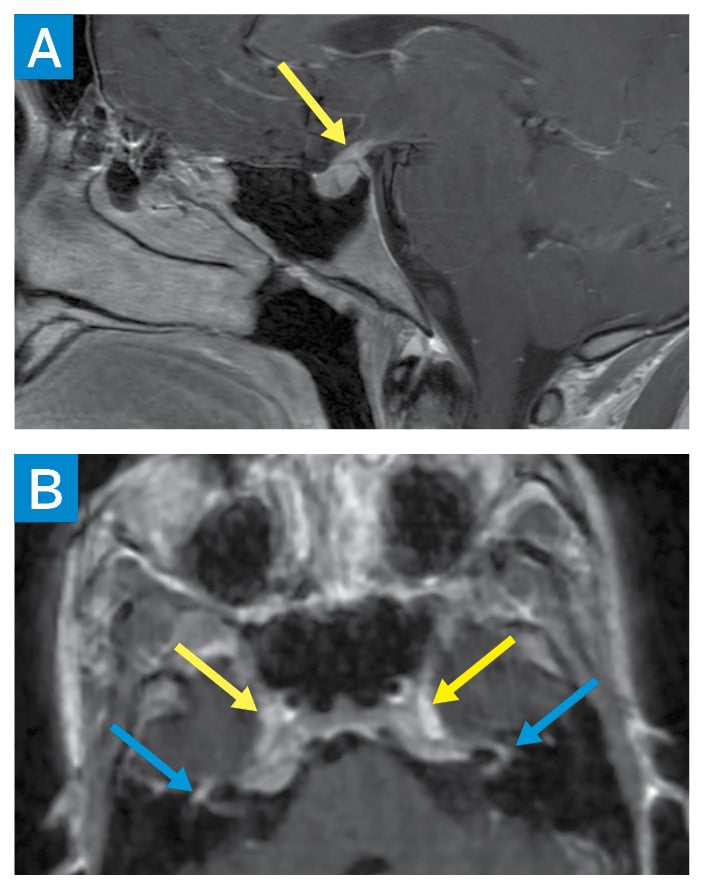

Subsequent studies revealed elevated serum angiotensin-converting enzyme (ACE), lysozyme, and interleukin-2 receptor levels, as well as low vitamin D-25OH, normal vitamin D-1,25OH, and a negative QuantiFERON-TB Gold assay. Bronchoscopic transbronchial lung biopsy showed non-necrotizing granulomas with negative acid-fast bacilli and fungal staining. Electrocardiography, continuous telemetry, and cardiac magnetic resonance imaging (MRI) were unrevealing. Brain MRI demonstrated thickening of the infundibulum and enhancement of bilateral facial nerves and Meckel’s caves (Fig. 2). Cerebrospinal fluid showed elevated protein and ACE levels.

Figure 2: Brain MRI showing sagittal postcontrast T1 image of the sella turcica with abnormal thickening of the pituitary infundibulum (yellow arrow) (A). Axial 3D T1 postcontrast facial nerves partially visualized within the internal auditory canals, labyrinthine segments, and geniculate ganglia (blue arrows) (B). Abnormal enhancement is also seen along the bilateral trigeminal nerve ganglia within the bilateral Meckel’s caves (yellow arrows).